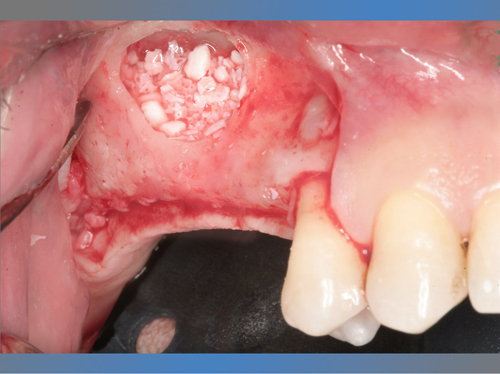

En el maxilar superior tenía poco hueso debido a la presencia del seno maxilar, por lo que se le trato con la técnica de injerto óseo conocida como elevación de seno directa para poder colocarle implantes.